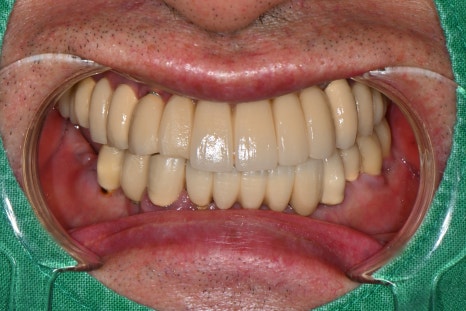

왼쪽 사진: 완성된 보철물의 정면 모습입니다. 심미성과 기능 모두 만족스럽게 회복되었습니다.

오른쪽 사진: 측면에서도 자연스러운 곡선과 교합이 잘 유지되어, 편안한 저작이 가능한 상태입니다.